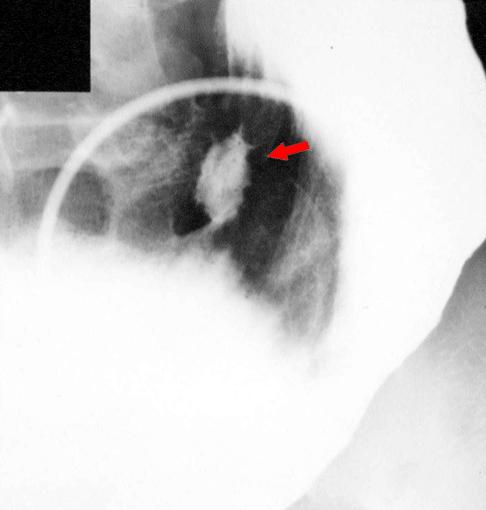

질환(병리주체)의 분류 악성 림프계종양/MLP형 악성 림프종

부위(장기별) 위(부위)/체부

검사방법 X-P

종양의 최대경(밀리미터) 20~24

다발종양(동일 장기) 유(동시성)